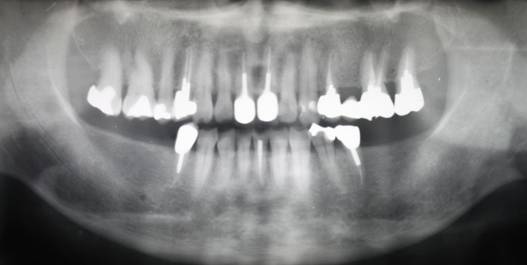

術前パノラマレントゲン写真。根の周りが黒くなり、骨がなくなっていることがわかります